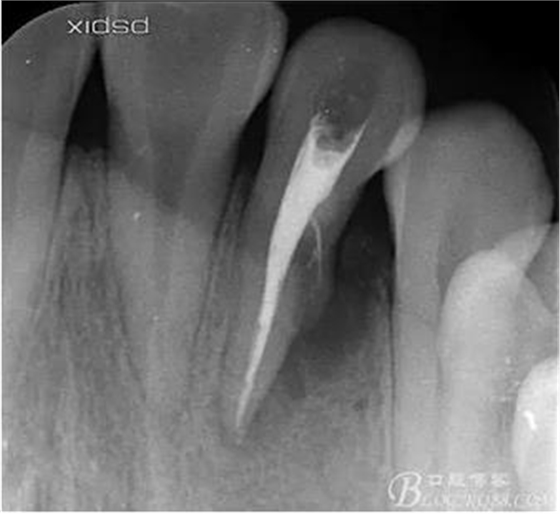

(1)檢查:12唇側(cè)牙齦可見竇道,牙體顏色較鄰牙暗,無光澤,形態(tài)完整無缺損,唇側(cè)及近遠(yuǎn)中向未提及牙周袋。腭側(cè)齦緣輕度紅腫,舌側(cè)窩可探及裂溝,可見浸墨狀痕跡,沿裂溝舌側(cè)探診牙周袋深大于11mm,除患牙外全口牙周狀況良好,為探及牙周袋,牙齦色粉紅。邊緣菲薄,質(zhì)地堅(jiān)韌。12冷熱診無反應(yīng),叩診(+-),無明顯松動(dòng),無咬合創(chuàng)傷。12根尖x線片示,根管中三分之一中可見一斜向線樣透射影像根尖區(qū)及遠(yuǎn)中根三分之一可見低密度透射暗影,錐形束CT示12根尖區(qū)唇腭向骨吸收已穿通,根面溝達(dá)根中三分之一卷曲分出另一牙根,再未見其他明顯的根管系統(tǒng)。

(2)診斷:12畸形根面溝合并牙周、牙髓聯(lián)合病變。